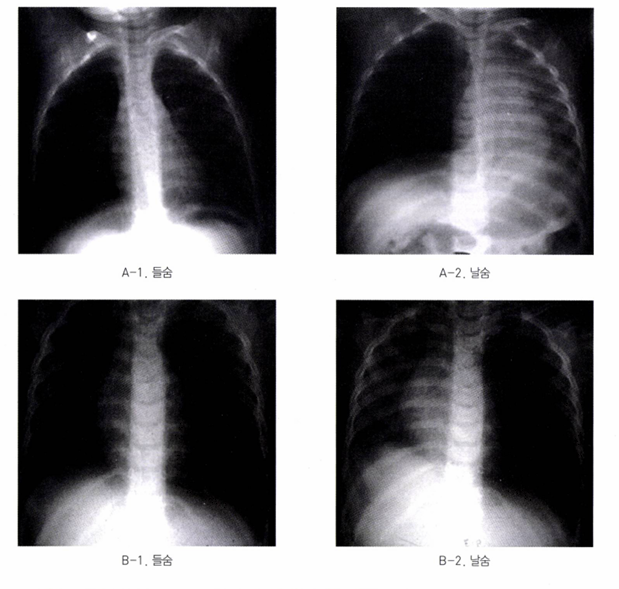

• 방사선 검사: 들숨 및 날숨 시의 흉부 X선(Chest X-ray)

• 이물이 공기를 가두는 '체크 밸브(check valve)' 효과를 일으킬 경우, 호기 시(expiration) 이물이 있는 쪽 폐의 과팽창(hyperinflation) 및 종격동 변위(mediastinal shift)가 관찰될 수 있음.

• 진단: 단순 X-ray, 투시 검사

• X-ray: 횡격막이 아래로 처져 평평하게 보이고, 늑골 간 간격 버어지며, 폐는 투명하게 보이고, 흉부의 전후 직경이 증가함

• 투시검사: 날숨 시 횡격막 움직임 감소